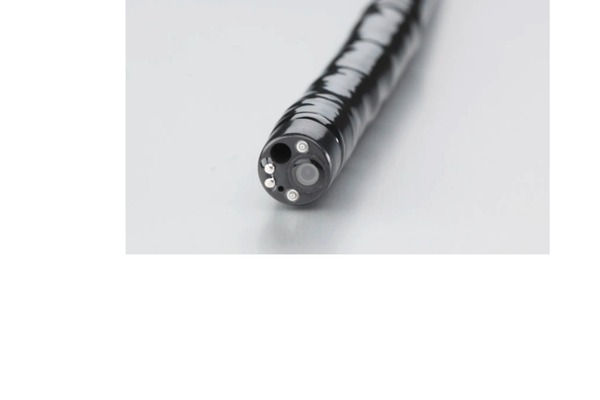

Stomach & Colon Endoscopy

Advanced diagnostic and therapeutic endoscopy procedures for the stomach and colon using the latest medical devices.

Small Bowel Capsule Endoscopy

Swallowable camera capsule to visualize the entire small intestine for bleeding, Crohn's, and tumors.